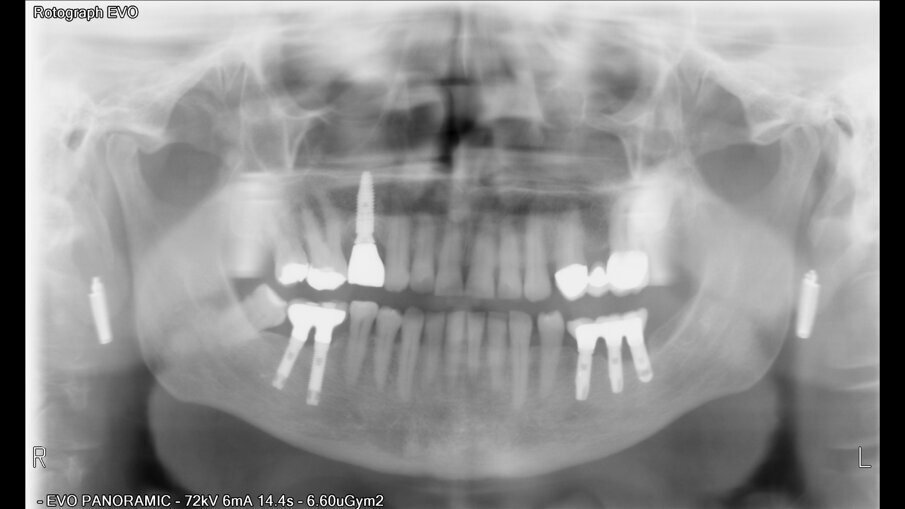

Posuzovali jsme 181 pacientů (97 žen a 121 mužů s průměrným věkem 49,2 let) se 721 implantáty. Z toho bylo zavedeno 384 implantátů na úrovni kosti, 289 zúžených implantátů na úrovni kosti a 48 implantátů na úrovni měkkých tkání (tabulka 2). Implantáty byly klasifikovány podle jejich pozice v horní a dolní čelisti. Pokud jde o anamnézu kouření u pacientů, počet denně vykouřených cigaret se pohyboval mezi 20 a 60 cigaretami.

Po chirurgickém zákroku byly pořízeny periapikální RTG snímky, na nichž byla zkontrolována přesnost zavedení implantátů. Pooperační medikace spočívala v předepsání antibiotik. Digitální RTG snímky byly pořízeny v době chirurgického zákroku, po 24 hodinách a jeden měsíc po zákroku, a to za účelem vyhodnocení úspěšnosti implantologického ošetření. Zánětlivé procesy byly zjištěny u 24,1 % pacientů. V případě potřeby byla provedena augmentace za použití materiálu NanoBone (Artoss), kostní náhražky Geistlich Bio­Oss a membrán Geistlich Bio-Gide (oba produkty Geistlich Biomaterials).

Ze 721 implantátů selhalo celkem 65 implantátů. Míra úspěšnosti tedy ve výsledku byla 90,98 %, tedy nižší než v naší předchozí studii provedené u nekuřáků, u nichž byla míra úspěšnosti 98,70 %.2 U skupiny neúspěšných implantátů selhala většina z nich (74,5 %) dva až čtyři týdny po zavedení v důsledku nedostatečné oseointegrace. Periimplantitida se vyskytovala u 20 % neúspěšných implantátů. To lze přičíst špatné ústní hygieně a tvorbě plaku. U 4,6 % případů se periimplantitida objevila v rozmezí jednoho až tří let po zavedení implantátu v důsledku mechanických problémů po úbytku kosti. Nebyla zjištěna žádná souvislost mezi délkou a průměrem implantátu a mírou selhání, ani mezi počtem vykouřených cigaret a mírou selhání implantátu.